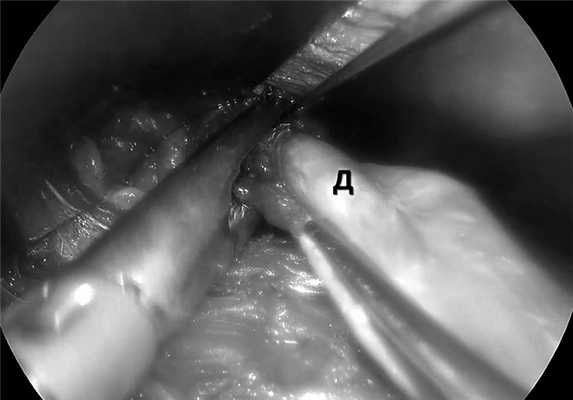

10.04.20 произведена операция. Положение пациента на спине с отведенной вверх и несколько вправо левой рукой. Под общим обезболиванием после предварительной разметки (рис. 2) выполнен доступ в левой подмышечной области длиной 5 см параллельно латеральному краю большой грудной мышцы. Отсепарован кожный лоскут вдоль грудной мышцы по направлению к нижней части шеи. После идентификации грудиноключично-сосцевидной мышцы доступ смещен по ее латеральному краю. Мышца отведена кверху при помощи средостенного ретрактора. Для контроля дальнейших манипуляций применяли эндоскопическую оптику (10 мм, 30°). Мобилизацию осуществляли при помощи ультразвуковых ножниц (Harmonic Ace + Shears, «Ethicon»). Идентифицированы лопаточно-подъязычная мышца, общая сонная артерия и яремная вена, которые отведены в сторону. Тупым и острым путем выделена левая доля щитовидной железы и отведена вверх. При этом отчетливо идентифицирован левый возвратный гортанный нерв. Дополнительно выделена и пересечена верхняя щитовидная артерия. Выявлен глоточно-пищеводный дивертикул, выделен из окружающих тканей на задней части глотки до шейки (рис. 3). Через подмышечный доступ ввели эндоскопический линейный сшивающий аппарат Echelon Flex 45 («Ethicon») с синей кассетой (рис. 4). Выполнено интраоперационное эндоскопическое исследование, осмотрено устье дивертикула и подтверждена правильность позиционирования аппарата для предотвращения сужения глотки и пищевода. Дивертикул прошит и отсечен. Дефект мышечной стенки ушит отдельными узловыми швами (Vicryl 3/0, «Ethicon») с помощью эндоскопических иглодержателей.

Рис. 4. Позиционирование эндоскопического сшивающего аппарата перед прошиванием и отсечением дивертикула (интраоперационная фотография).